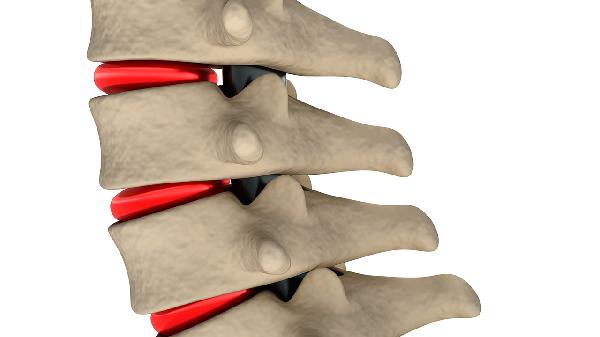

脊柱由26块椎骨组成,椎间盘含水量在晨起时较高,通过游泳、悬垂等拉伸运动可暂时增加椎间隙厚度。游泳时水的浮力能减轻关节压力,自由泳和仰泳对脊柱拉伸效果较好,每周进行3次30分钟游泳可维持椎间盘弹性。悬垂运动利用自重牵引脊柱,每天坚持2组每组15秒能改善轻微驼背。瑜伽中的山式站立和猫牛式可增强核心肌群稳定性,减少日常姿势不良造成的身高压缩。